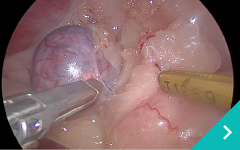

東京どうぶつ低侵襲医療センターでは、大切なご家族である動物たちの体への負担をできる限り軽減するために、 低侵襲(ていしんしゅう)技術を用いた診断・治療を行っています。 内視鏡や腹腔鏡、血管内治療などの先進的な医療機器と専門知識を駆使し、「きずが小さく、痛みが少ない」ことを追求。 術後の回復も早く、入院期間の短縮にもつながります。また、各分野の専門獣医師が連携し、安心・安全なチーム医療を提供しています。

動物たちにやさしく、飼い主さまにも安心していただける医療を目指しています。

肝臓・胆嚢・膵臓 専門診療

肝臓・胆嚢・膵臓疾患の専門医による外来診療を、月に一度実施しております。

高度な判断と治療が求められる症例にも、安心してご相談いただけます。

肝臓胆嚢膵臓と腹腔鏡の専門医(鳥巣、重本)が診療いたします。

腹腔鏡胸腔鏡

診療科目:腹腔鏡・胸腔鏡

『傷』が小さく、『痛み』が少ない手術・検査ができます!!

内視鏡外科(低侵襲)を希望のかたは東京どうぶつ低侵襲医療センター・王子ペットクリニックに相談ください。